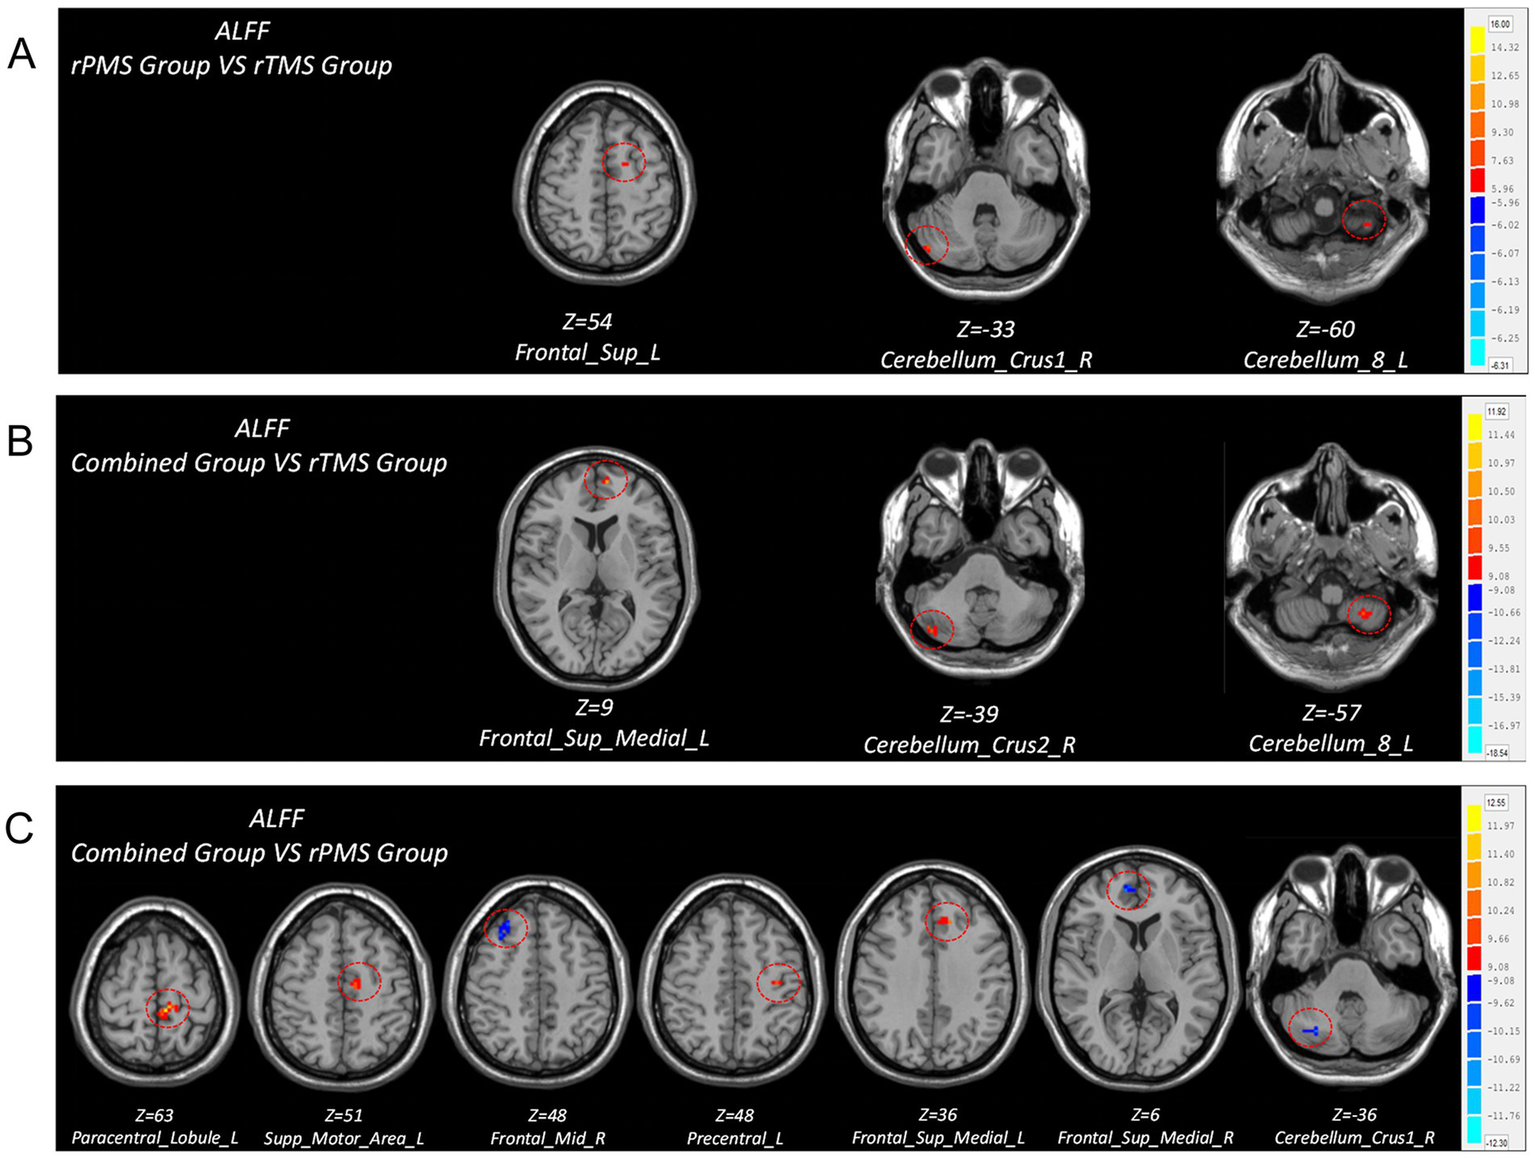

(2) Group comparison

Compared to the rTMS group, the post-hoc analyses revealed that the rPMS group showed increased ALFF in the ipsilesional superior frontal gyrus, cerebellum_8 area, and contralesional cerebellum_crus1 area post-intervention; the combined group showed increased ALFF in the ipsilesional cerebellum_8 area, superior medial frontal gyrus, and contralesional cerebellum_crus2 area post-intervention. Compared to the rPMS group, the combined group showed increased ALFF in the ipsilesional paracentral lobule, SMA, precentral gyrus, and superior medial frontal gyrus and decreased ALFF in the contralesional cerebellum_crus1 area, superior medial frontal gyrus, and middle frontal gyrus post-intervention (Table 5; Figure 4).

Figure 4

Brain regions with differences in ALFF values after treatment among three groups. (A) Comparison of ALFF differences between rPMS group and rTMS group. (B) Comparison of ALFF differences between combined group and rTMS group. (C) Comparison of ALFF differences between combined group and rPMS group.